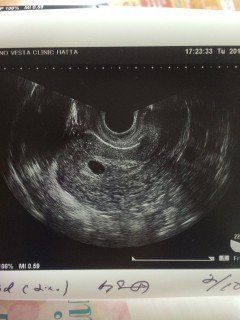

エコー前に先生が、5w になったばかりだから見えなくても泣かないでね!と言ってました。 すぐに小さい黒マルが確認できて嬉しかったぁ! まだ5. 4㎜と極小なので、次回はもっと大きく育っていて欲しいです♪